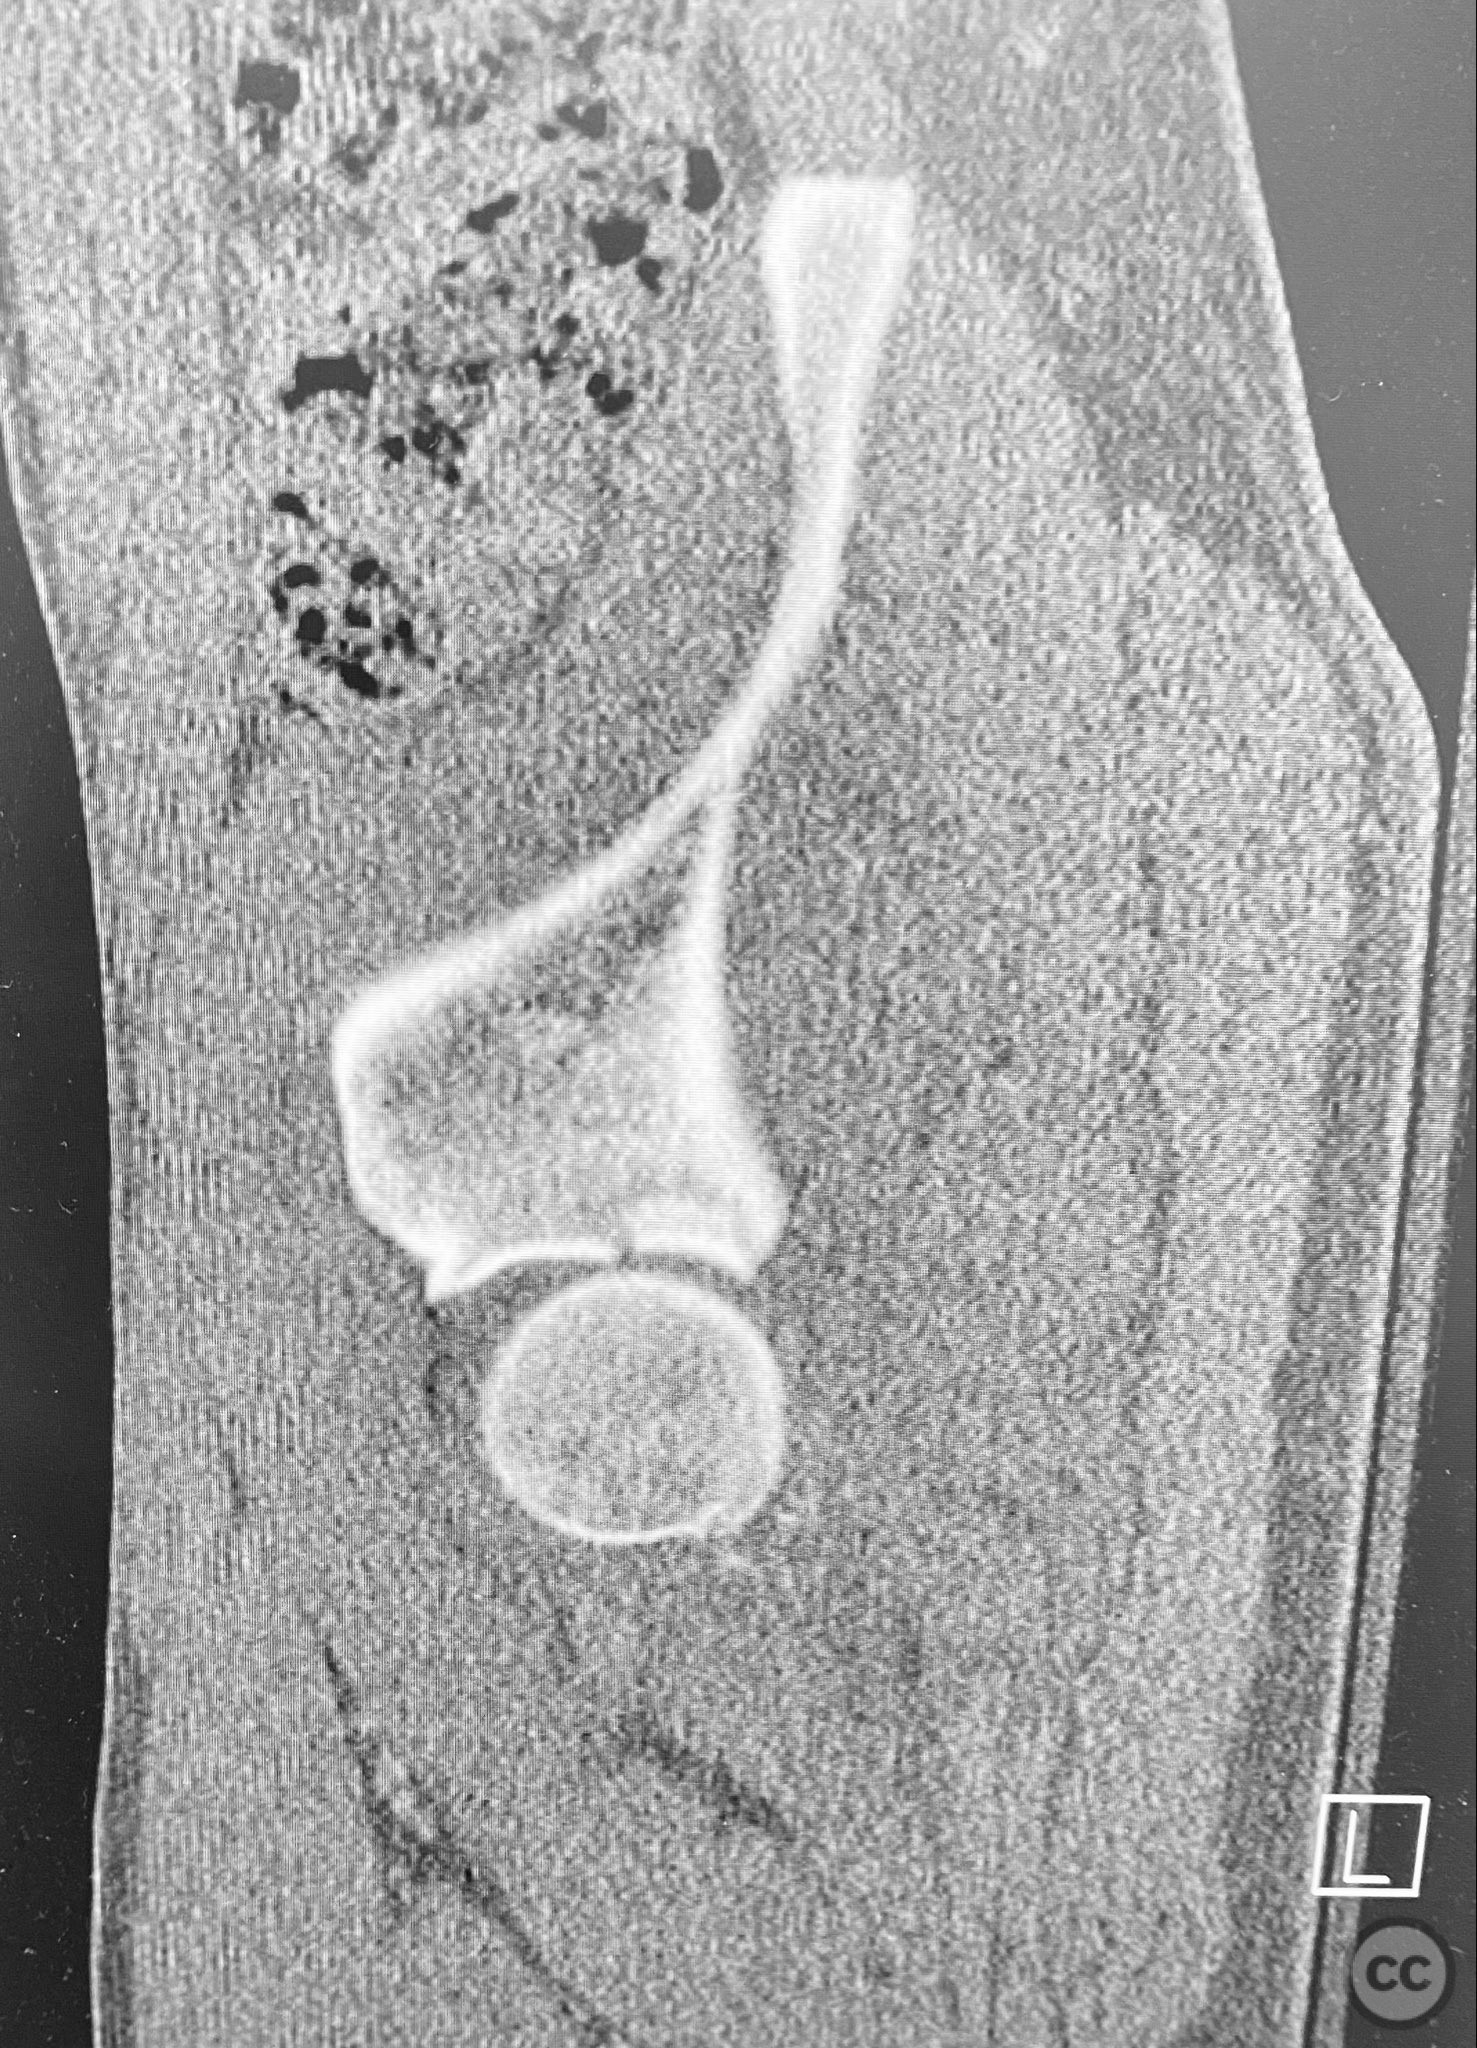

Patient positioning:  The patient was positioned prone on a radiolucent table, with all pressure points padded. Skeletal traction was maintained via a distal femoral K-wire and tensioning bow throughout the procedure.

The initial failed closed reduction likely resulted from interposed soft tissue or bony fragments, or inadequate sedation/muscle relaxation. Repeat reduction under improved conditions was successful prior to definitive fixation. 3D CT renderings provided enhanced visualization of impaction zones and comminution, facilitating preoperative planning for grafting and fragment-specific fixation. Intraoperatively, elevation of the impacted dome required careful manipulation to avoid further chondral injury. Use of a spring hook plate provided secure fixation of the cranial wall fragment, while the reconstruction plate supported the main wall fragment. Postoperative CT confirmed satisfactory reduction and implant positioning.

Orthopaedic implants used:   Spring hook plate; 3.5mm reconstruction plate; autologous trochanteric bone graft; distal femoral K-wire (for skeletal traction)